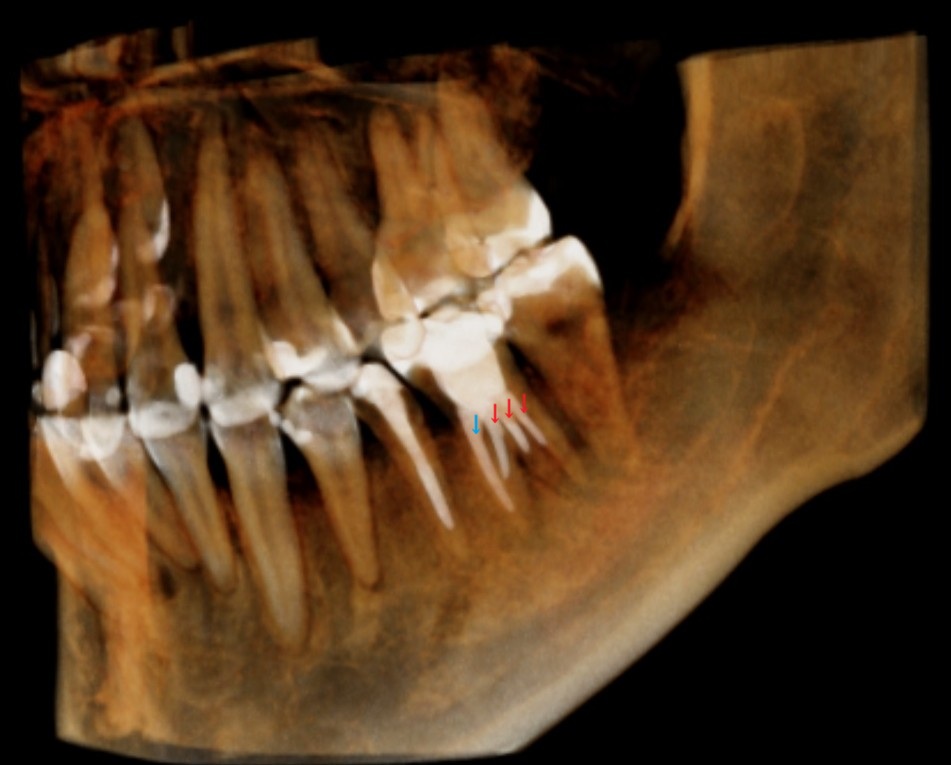

CT撮影です。

下の6番目の歯で、2本の根があります。

それぞれの根の先に黒い影があります。根の先で膿んで顎の骨が溶けています。

CTの3D画像で確認してみましょう。

根管に入れた材料(充填材)が白く写っています。

青い矢印のみ長く先端まで伸びていて、赤い矢印3本は途中で止まっているのが分かります。